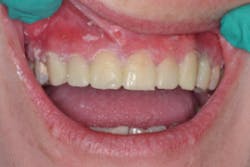

Finally, the moment of truth came. I looked to the ceiling, then to my assistant, and said, “Please work.” I popped the matrix off the teeth and ... behold ... teeth! See Figure 6.

Using just a scaler, I quickly and easily removed almost all of the excess to a perfect marginal finish. However, there were two remaining clinical concerns: 1. All of the teeth were bonded together, which was fine if they were veneer temps—but not final restorations, and 2. if I separated the teeth, I would be left with gaps. So, this is what I decided to do.

Using a Microcopy XF flame-shaped diamond, I opened up any overfilled embrasures, which required minimal effort thanks to a detailed matrix. Using QwikStrip serrated and polishing strips, I separated each of the teeth proximally and polished them. As anticipated, the proximal contacts for teeth Nos. 5–12 were light. To tighten the contacts post-operatively, I left the centric occlusal stops on Nos. 6–11 lighter than the occlusal stops of the posterior teeth (figure 7).